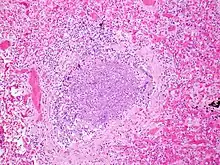

.jpg.webp)

The term usually refers to acute viral bronchiolitis, a common disease in infancy. This is most commonly caused by respiratory syncytial virus[12] (RSV, also known as human pneumovirus). Other agents that cause this illness include human metapneumovirus, influenza, parainfluenza, coronavirus, adenovirus, rhinovirus and mycoplasma.[13][14]